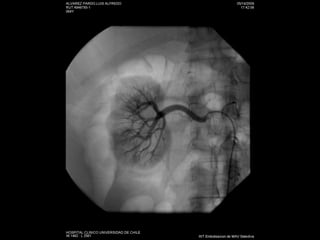

Angiografía

Estudio No invasivo: AngioTC Doppler Angio RM:  esclerosis sistémica  nefrogénica Invasivo: angiografía

Stent y plastias de estenosis